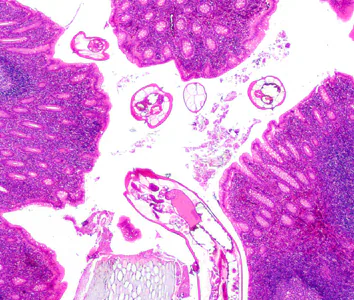

A ten-year-old boy presented at a local hospital with symptoms mimicking an appendicitis. An appendectomy was performed and biopsy specimens were sent to Pathology for routine histologic work-up. Objects suggestive of a parasite were observed by the attending pathologist. Figures A–E show what was observed on a slide stained with hematoxylin-and-eosin (H&E). What is your diagnosis? Based on what criteria?

Figure A